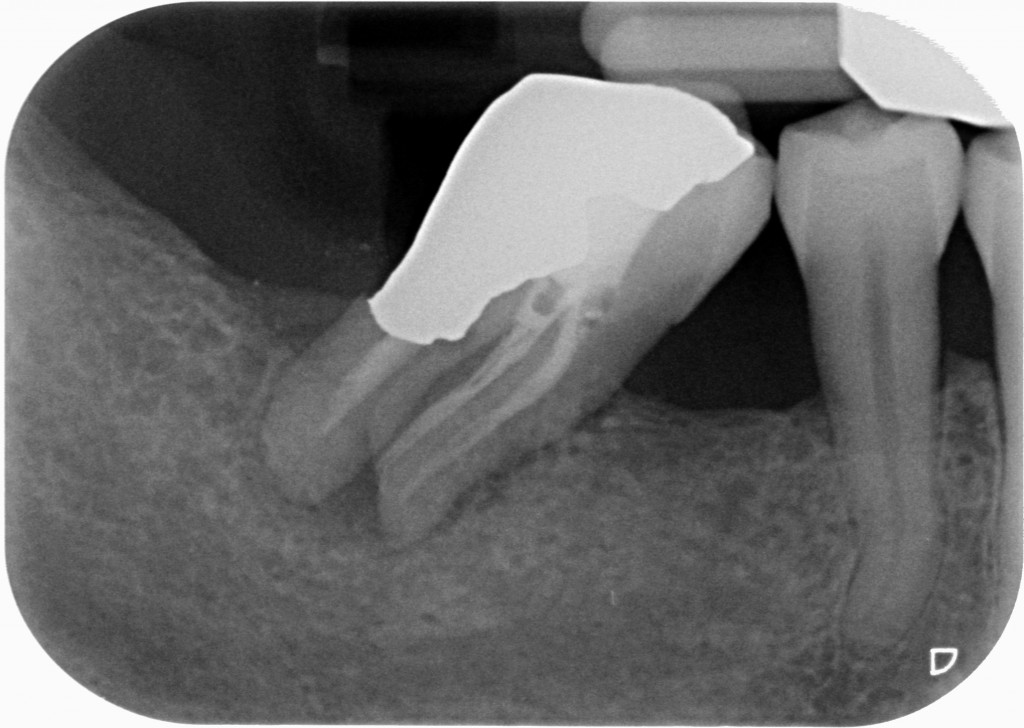

Se invadere l’ampiezza biologica massacra l’osso e genera tasche spiegami perchè in queste due rx scattate a 4 anni di distanza tra loro, l’osso distale al 4.7 mesializzato, che sarà da estrarre per altri motivi, sia sempre uguale, con un risentimento legato alla carie primaria che c’era stata verosimilmente decenni prima…?

Come puoi vedere dalle immagini qui sotto, il caso che ho mostrato nella rx precedente a 4 anni di distanza mostra che nè l’osso nè la papilla risentono di questo terribile insulto…